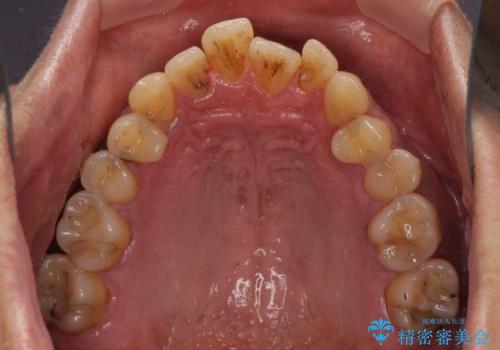

前歯のクロスバイトを改善 ワイヤー装置での非抜歯矯正

- 骨格的な咬み合わせのズレ、前歯のデコボコとクロスバイトを気にして来院された患者様です。

骨格のズレが顕著であると診断され、マウスピース矯正では奥歯の咬み合わせが整えにくいと判断し、ワイヤー装置による矯正治療を行うこととしました。

上下の叢生は速やかに改善できましたが、右側のクロスバイトの改善に1年以上の期間を要しました。